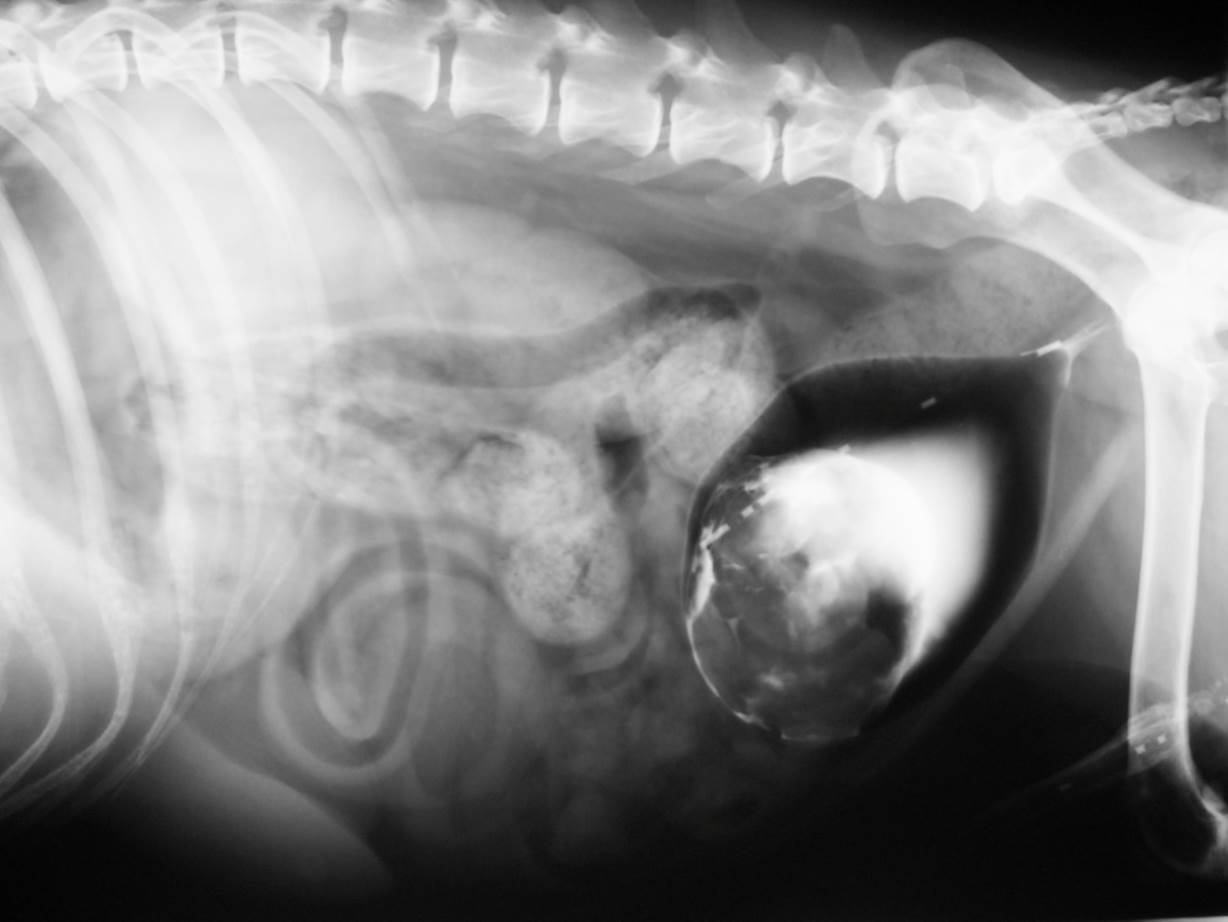

Case Chewbacca

Discuss this case?

–visible on the lateral and VD views

–visible at different time points during the study